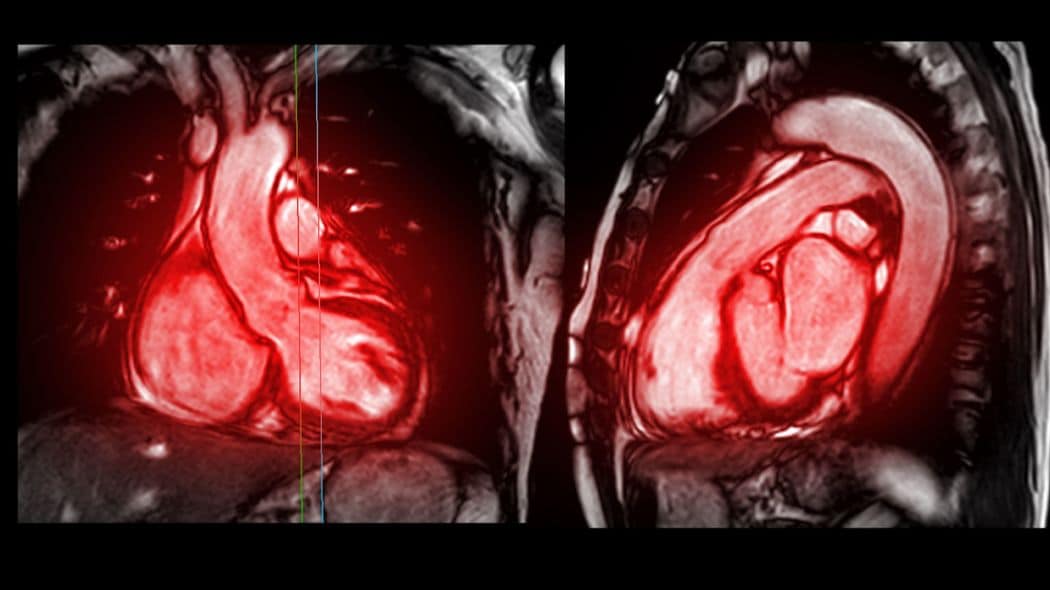

母親はこの他にも、半年に1回、大動脈瘤やリンパ腫などの予後の確認のため、総合病院でCT検査を受けていただけでなく、皮膚科や整形外科などの受診が必要になることも。その際は、冬木さんが建設会社の派遣の仕事の休みを取って付き添っていた。